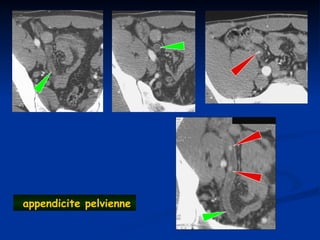

appendicite pelvienne